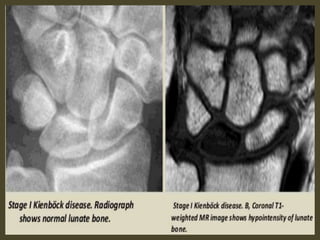

Keinbock,s Disease.